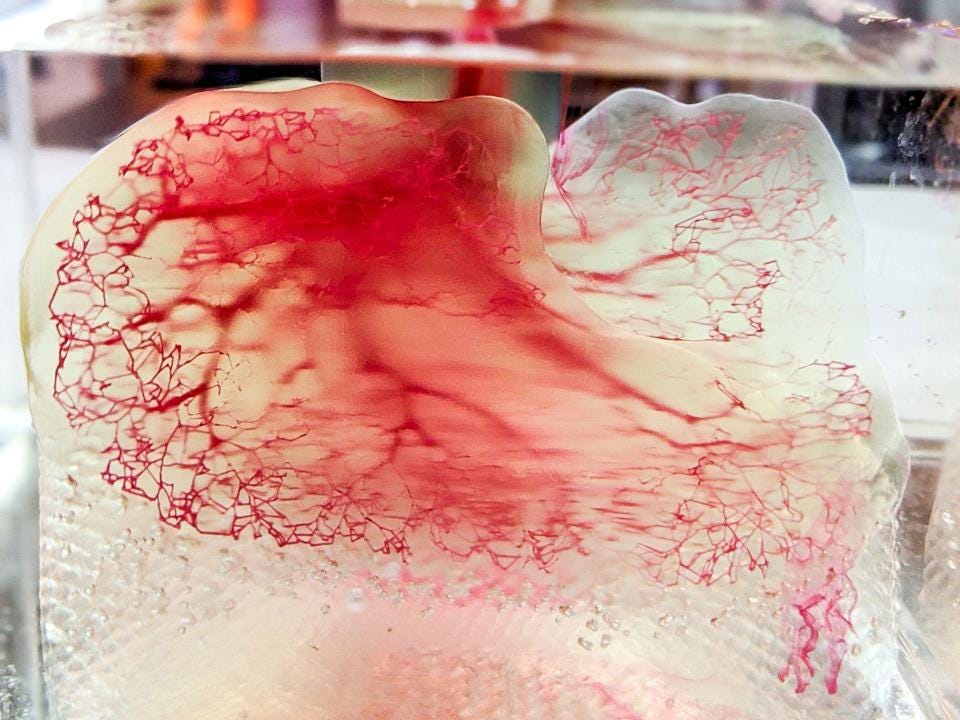

Una stampante 3D in grado di riprodurre organi umani perfettamente funzioti e pronti per essere trapiantati. Questa in breve la rivoluzione messa in atto dai ricercatori della Solid World, una società biomedicale che nasce dall’Università di Pisa, una delle principali realtà italiane specializzate nella stampa 3D.

Il team di lavoro, è stato in grado di brevettare un macchinario capace di biostampare parti di organi umani a partire da una soluzione acquosa, contenente le cellule del paziente. Gli organi così prodotti, possono essere utilizzati senza rischio di rigetto nel paziente che necessita un trapianto.

Electro Spider, questo il suo nome, è un’apparecchiatura rivoluzionaria che nel breve termine sarà in grado di di stampare per intero organi molto complessi come fegato, reni e cuore. Ad oggi, la stampante di organi 3D è in fase di test su delle componenti di organi, ma gli sviluppi sembrano positivi e la sua commercializzazione è prevista per il 2022.

La tecnica utilizzata per riprodurre parti di organi umani è chiamata bioprinting o biostampa in italiano ed è molto simile alla stampa 3D in cui si utilizza un modello digitale per creare un oggetto tridimensionale strato dopo strato. Al posto di plastica, metallo o polveri, la biostampa fa uso di “bioinchiostro”, una sorta di gel contenente cellule viventi.

I primi esperimenti sono partiti con la produzione di frammenti di cartilagine o pelle. Oggi la ricerca ha fatto grandi progressi e siamo in grado di produrre parti di organi vitali come polmoni, cuori e fegato.